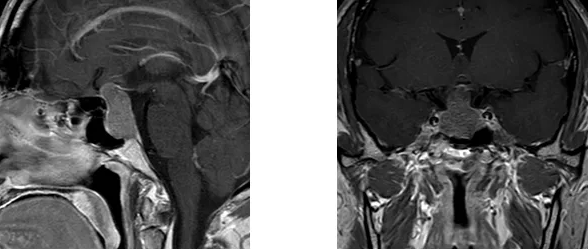

"眼前突然模糊的那一刻,我知道这不是疲劳。"作为河南省某三甲医院外科主任,刘主任(化名)在连续完成多台高难度手术后,敏锐察觉到自己双眼视野缺损。头颅MRI检查结果令人心惊:鞍区赫然盘踞着直径3.5cm的巨大垂体腺瘤,视交叉结构已被严重挤压变形。

"3厘米以上的垂体瘤即可定义为巨大肿瘤,而视交叉受压超过3个月将造成不可逆损伤。"郑州大学第五附属医院神经外科一病区主刀专家寿记新主任解释。这位常年拯救患者的医者,此刻比任何人都清楚——这是一场与时间的赛跑。